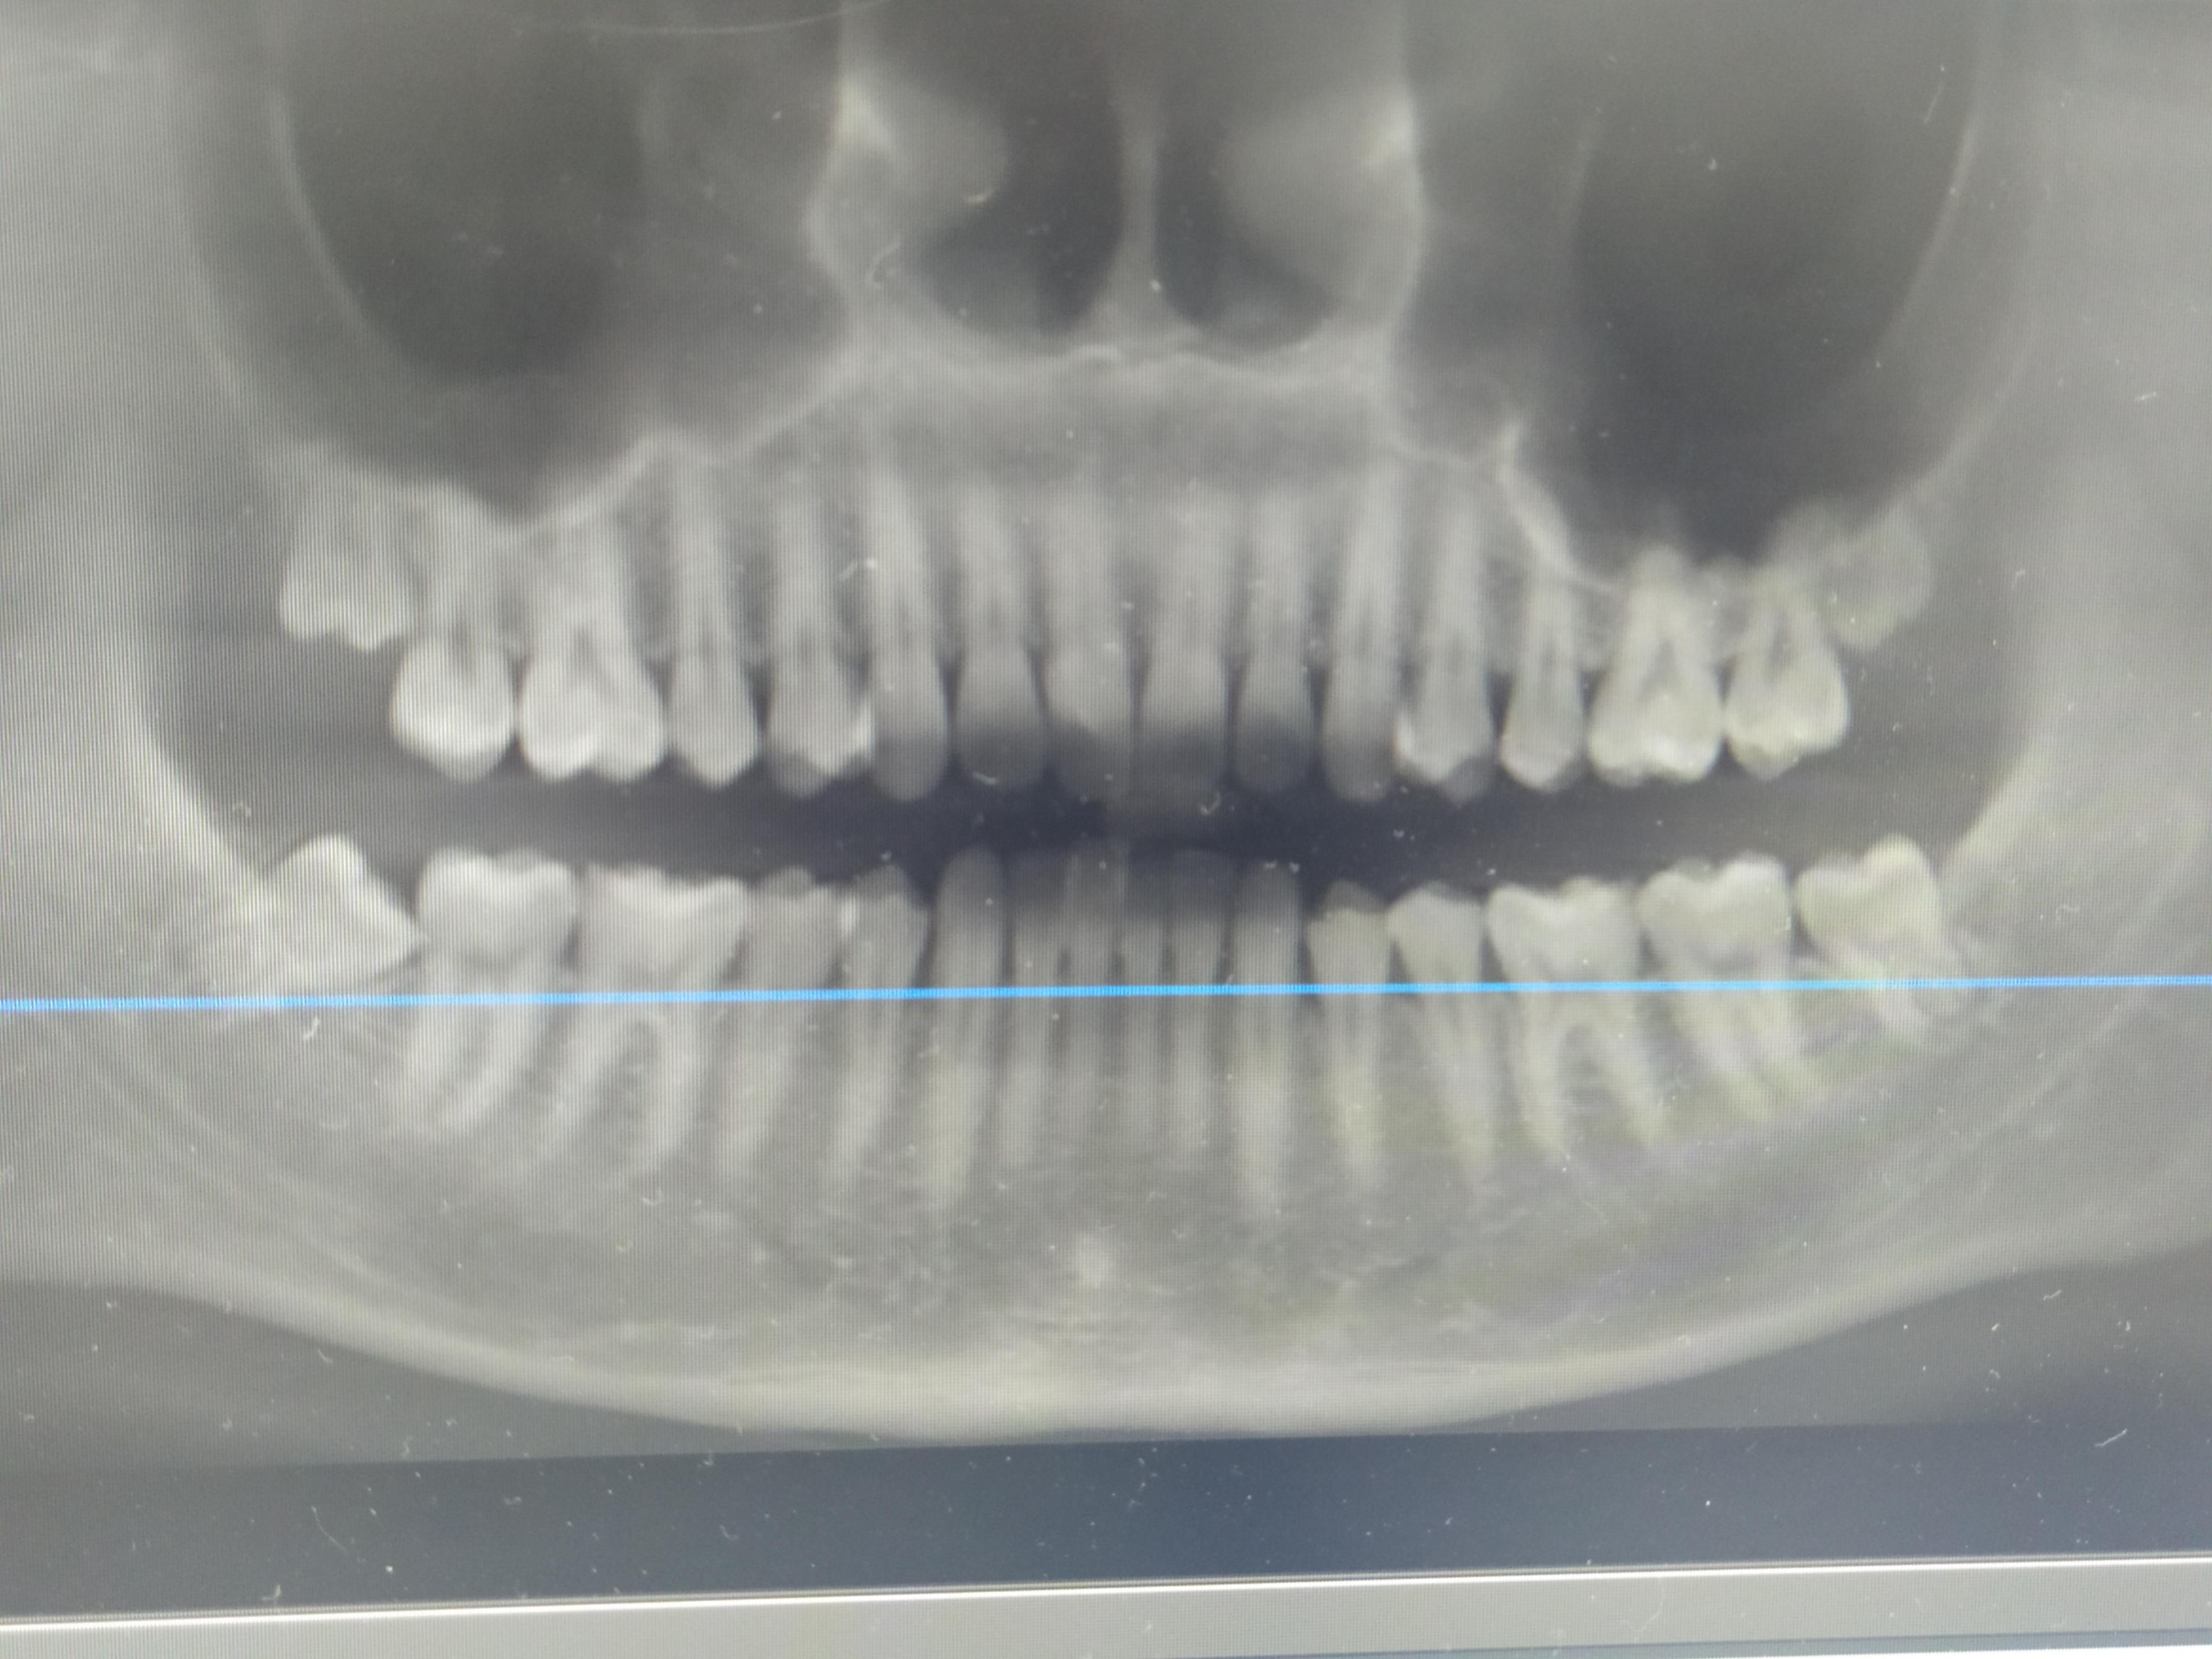

Очень давно мучает вопрос насчёт зубов мудрости. Насколько сильно может измениться челюсть после удаления? Уже идёт искривление (один передний зуб снизу ушел назад, а верхние передние начали чуть чуть сдвигаться) Может ли уменьшится челюсть после удаления мудрых зубов?